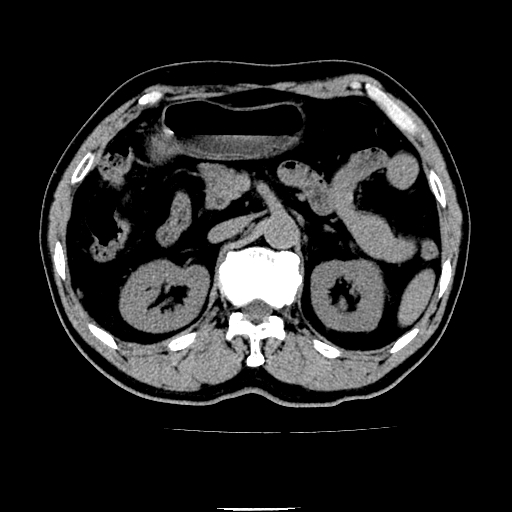

以下是引用chenqiong在2010-3-25 20:56:00的发言:[br]1、胆囊炎,胆囊息肉[br]2、肝内胆管及胆总管扩张,胆总管下端结石[br]3、十二指肠乳头旁憩室

以下是引用zxl51642在2010-3-26 10:47:00的发言:[br]胆囊炎,胆囊息肉,胆总管扩张,但未看到明显肿块,肝内胆管扩张不像恶性,炎性狭窄或阴性结石可能吧,建议mrcp,右肾小囊肿